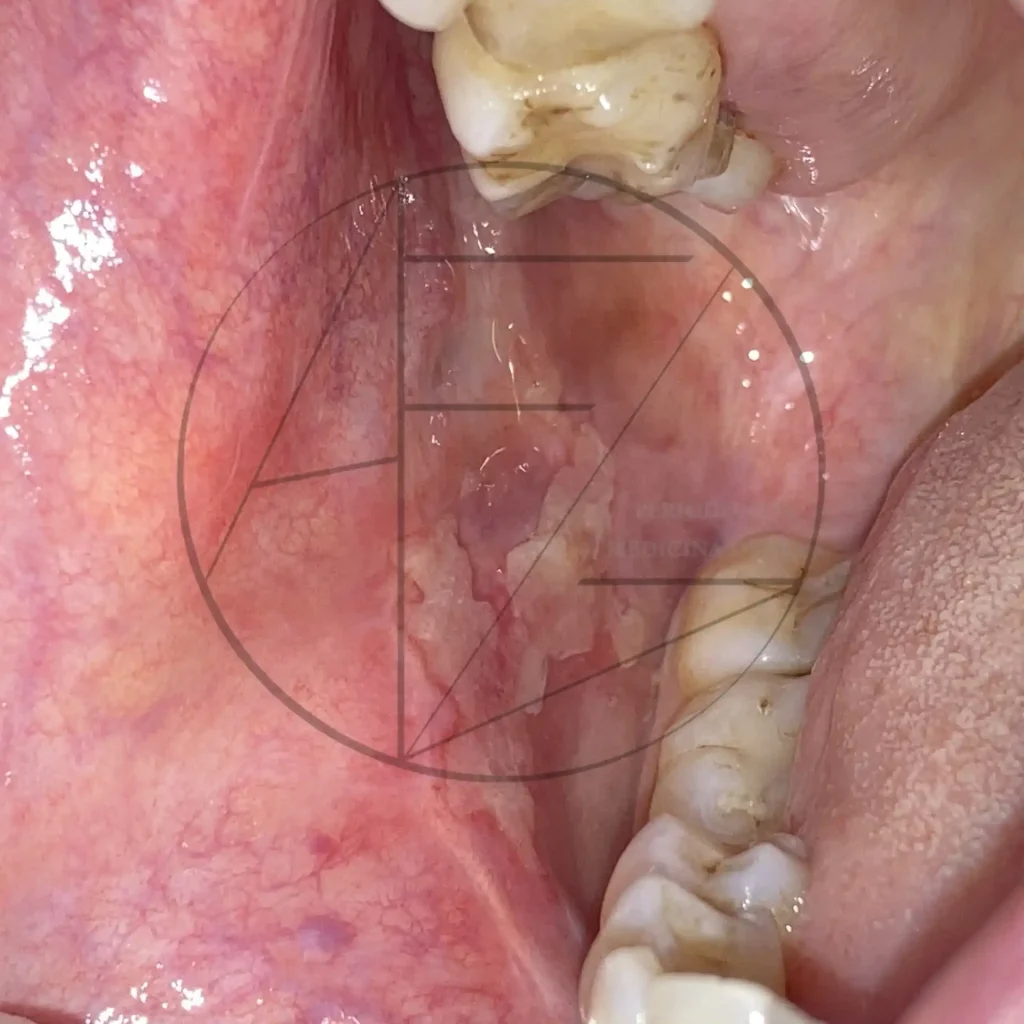

Casos clínicos

Fotos clínicas

Medicina Oral y Preventiva

La medicina oral se ocupa del estudio, diagnóstico y tratamiento de las enfermedades de la boca y de las estructuras relacionadas, como mucosa oral, lengua, glándulas salivales y articulación temporomandibular. También aborda la detección precoz de lesiones potencialmente malignas, infecciones, alteraciones de la saliva y complicaciones orales relacionadas con enfermedades sistémicas o tratamientos médicos.